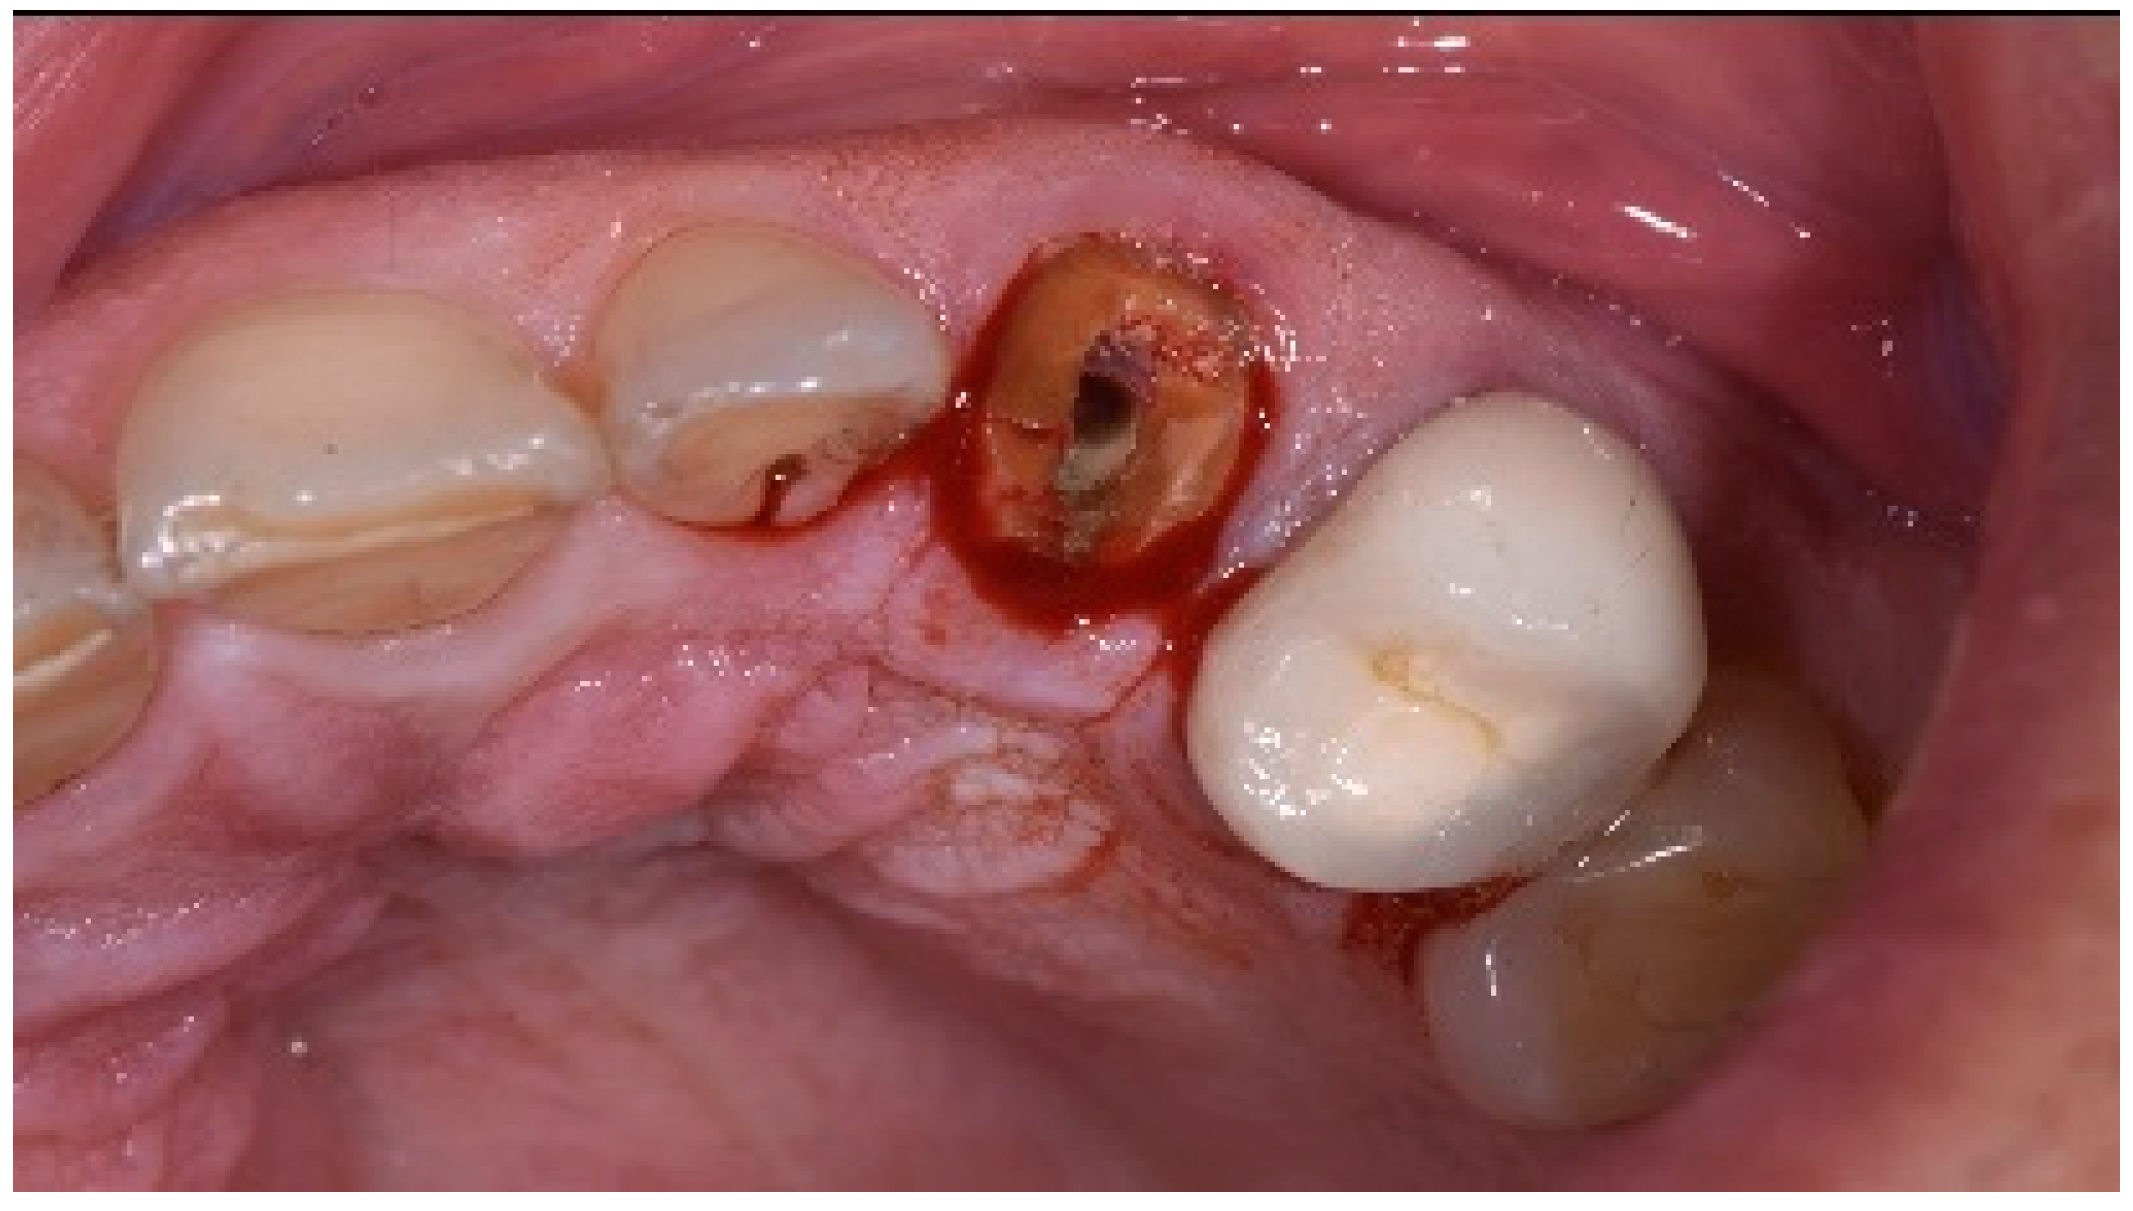

A 43-year-old female patient in good health and a non-smoker presented with a history of endodontic failure of the maxillary central incisors. She was interested in the replacement of her teeth with endosseous implants. The teeth had previously been treated endodontically with no lesion regression. Endodontic surgery had also failed. Clinical examination revealed class 1 mobility and a scar on the soft tissue above the maxillary anterior teeth. Radiographic examinations revealed the presence of chronic periapical lesions associated with teeth number 8 and 9, and clinically there was minimal remaining tooth structure (Figure 1). A treatment plan involving the placement of two immediate implants followed by future ceramic crowns was presented and accepted by the patient.

Figure 1.

Clinical view of existing maxillary incisors.